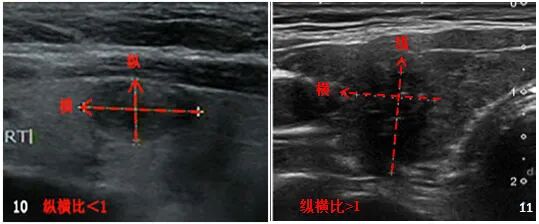

第三步:看结节形状

结节按形状来分:可分为规则形状和不规则形状。 规则形状又分为:椭圆形或椭圆形、圆形和立形。 不规则形状包括:叶状和毛刺状(见下图)。

临床上常采用纵横比(即横切面上前后径与左右径的比值)来衡量结节形态。 纵横比 >1 对于预测乳头状癌具有高度特异性(图 10-11)。

图10:人民日报发表的《超声影像报告标准及数据系统分析》

图11:2017年ETA指南“成人甲状腺结节超声恶性风险分层”